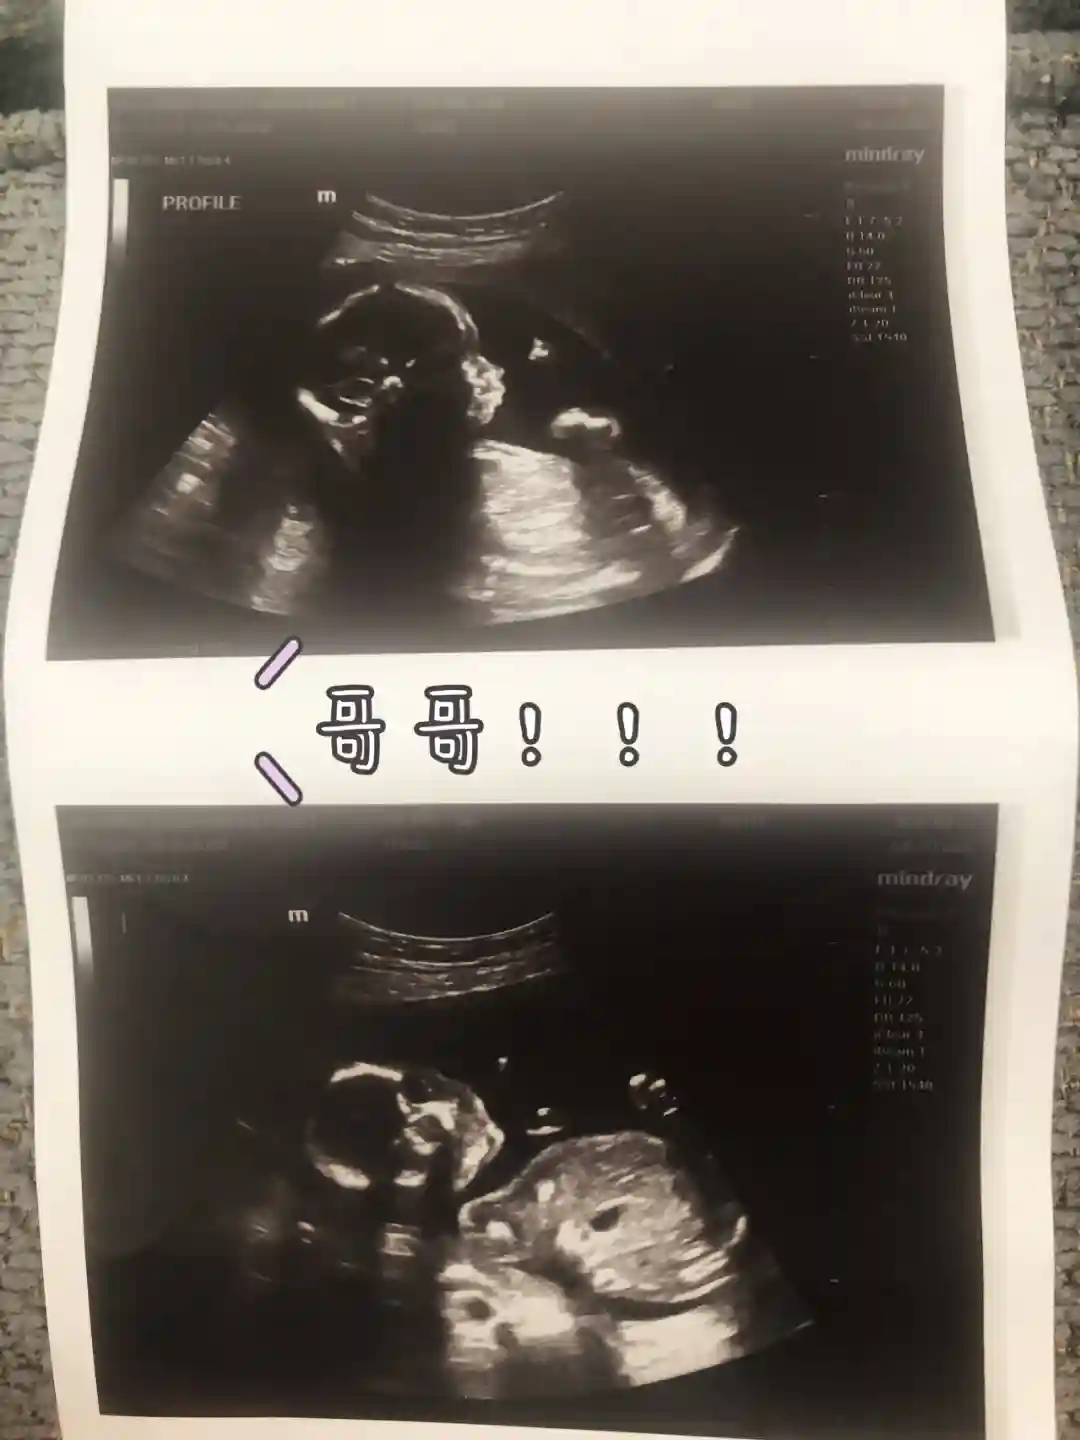

一胎是在刚搬进新房没几个月,大姨妈延期很久买验孕棒查出来的,由于我姨妈通常都不准时,所以一开始并没在意,还去溜冰摔到屁股疼,大条妈妈上线!怀孕前三个月觉得累和嗜睡,胃口一般其他还好没有特别的不适感。三个月后基本和没事人一样啦!4个多月去死亡谷玩了一下,怀孕怕晒,太热就容易头昏脑胀。6个月还去斯坦福参加了表妹婚礼,不说人家都不知道我怀孕。反正就是各种游山玩水逛街吃喝! 32周的时候出现了插曲,孕妈们都要注意啦。我开始身上痒,不是干燥皮肤紧绷那种痒,尤其晚上手心角心痒到不行,网上查了一下可能是胆汁淤积,(据说是胆汁进入到羊水里,造成羊水浑浊,容易造成胎儿窒息)于是立马告诉了自己的产科医生,马上验血,果然中了...除夕夜住院观察三天,就是每天检查胎心,吃药。出院后每天都要到医院报道抽血检查胎心。虽然基本稳定但是医生为了宝宝健康还是决定提前一个月引产。催产素然后无痛反正入院24小时后大斯丁BB安全落地,5斤多点很健康!